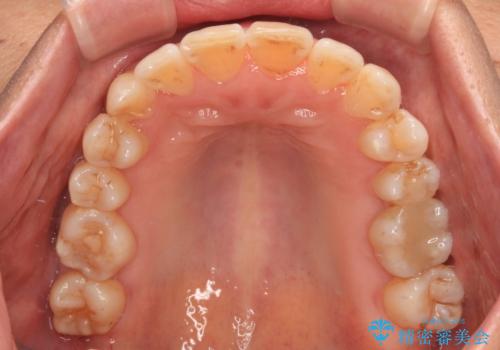

- 骨格的な咬み合わせのズレ、前歯のデコボコとクロスバイトを気にして来院された患者様です。

奥歯の噛みにくさが顕著なためマウスピースではなく、ワイヤー装置による矯正治療を行うこととしました。

下顎の正中を歯1本分ずらした位置とすることで、外見上の骨格的なずれをカバーするように計画しました。

クロスバイトを改善したことで、前歯の負担が軽減し、安定して噛めるようになりました。